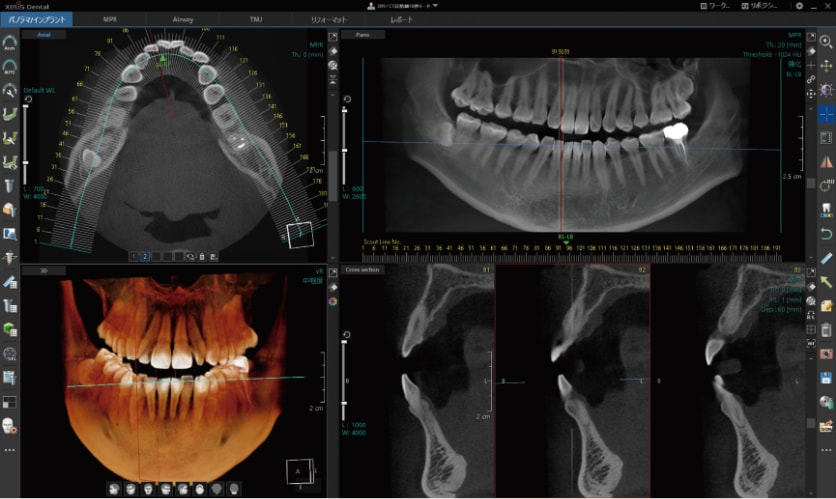

CT画像専用ビューアーソフト「 XelisDental(ゼリスデンタル )」

Pano/Implant、MPR、TMJの各種解析ツールをタブで切替できます。

タブの切替のみで、ツールアイコンが変化する為、迷わず操作が可能です。

歯科領域で必須とされる各解析ツールを搭載。

歯列弓や下顎管の抽出等のアナログな作業を軽減する、各種オート機能を搭載。

オートアーチ機能

任意のアキシャル画像をクリックするだけで、自動的にパノラマ画像が作成できます。

それと同時に、クロスセクショナル画像も作成されます。